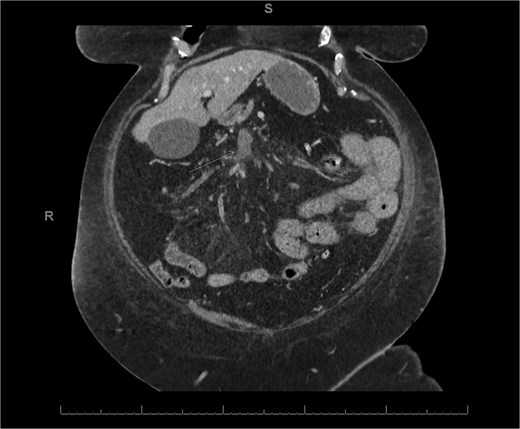

A 45-year-old male presenting with a 10-day history of isolated right lower quadrant (RLQ) abdominal pain. His history included deep vein thrombosis, coronary artery disease with prior STEMI, left anterior descending artery stenting in 2014, and ongoing antiplatelet therapy with aspirin. Upon admission, RLG tenderness was noted. Laboratory revealed leucocytosis (WBC 16 G/L) and elevated CRP (70 mg/L). E-CT revealed superior mesenteric and portal systems thrombosis with ischemia of a small bowel loop in the RLQ, characterized by absent bowel wall enhancement and free fluid (Fig. 4). Besides these findings, he was managed conservatively with a UFH bolus of 5000 U/l, followed by a continuous infusion of 36 000 U/l over 24 h (target INR 0. 35–0. 7), Ceftriaxone and Metronidazole, bowel rest, and ICU monitoring for 48 h. Clinical and biological improvement was rapid. E-CT on the second day showed no signs of perforation (Fig. 5). He was discharged after 7 days on LMWH (enoxaparin sodium 90 mg every 12 h). Twenty days later, he re-presented with acute RLQ pain and localized peritonism. E-CT revealed a covered perforation of the previously ischemic small bowel loop (Fig. 6). A segmental bowel resection with primary anastomosis was performed by laparotomy (Fig. 7). The postoperative course was uneventful, and he was discharged on postoperative day 4 with sodium enoxaparin 90 mg/12 h.

E-CT of the second patient 48 h after conservative management, showing no further complications, including no signs of perforation regarding the bowel wall located with dashed arrows.